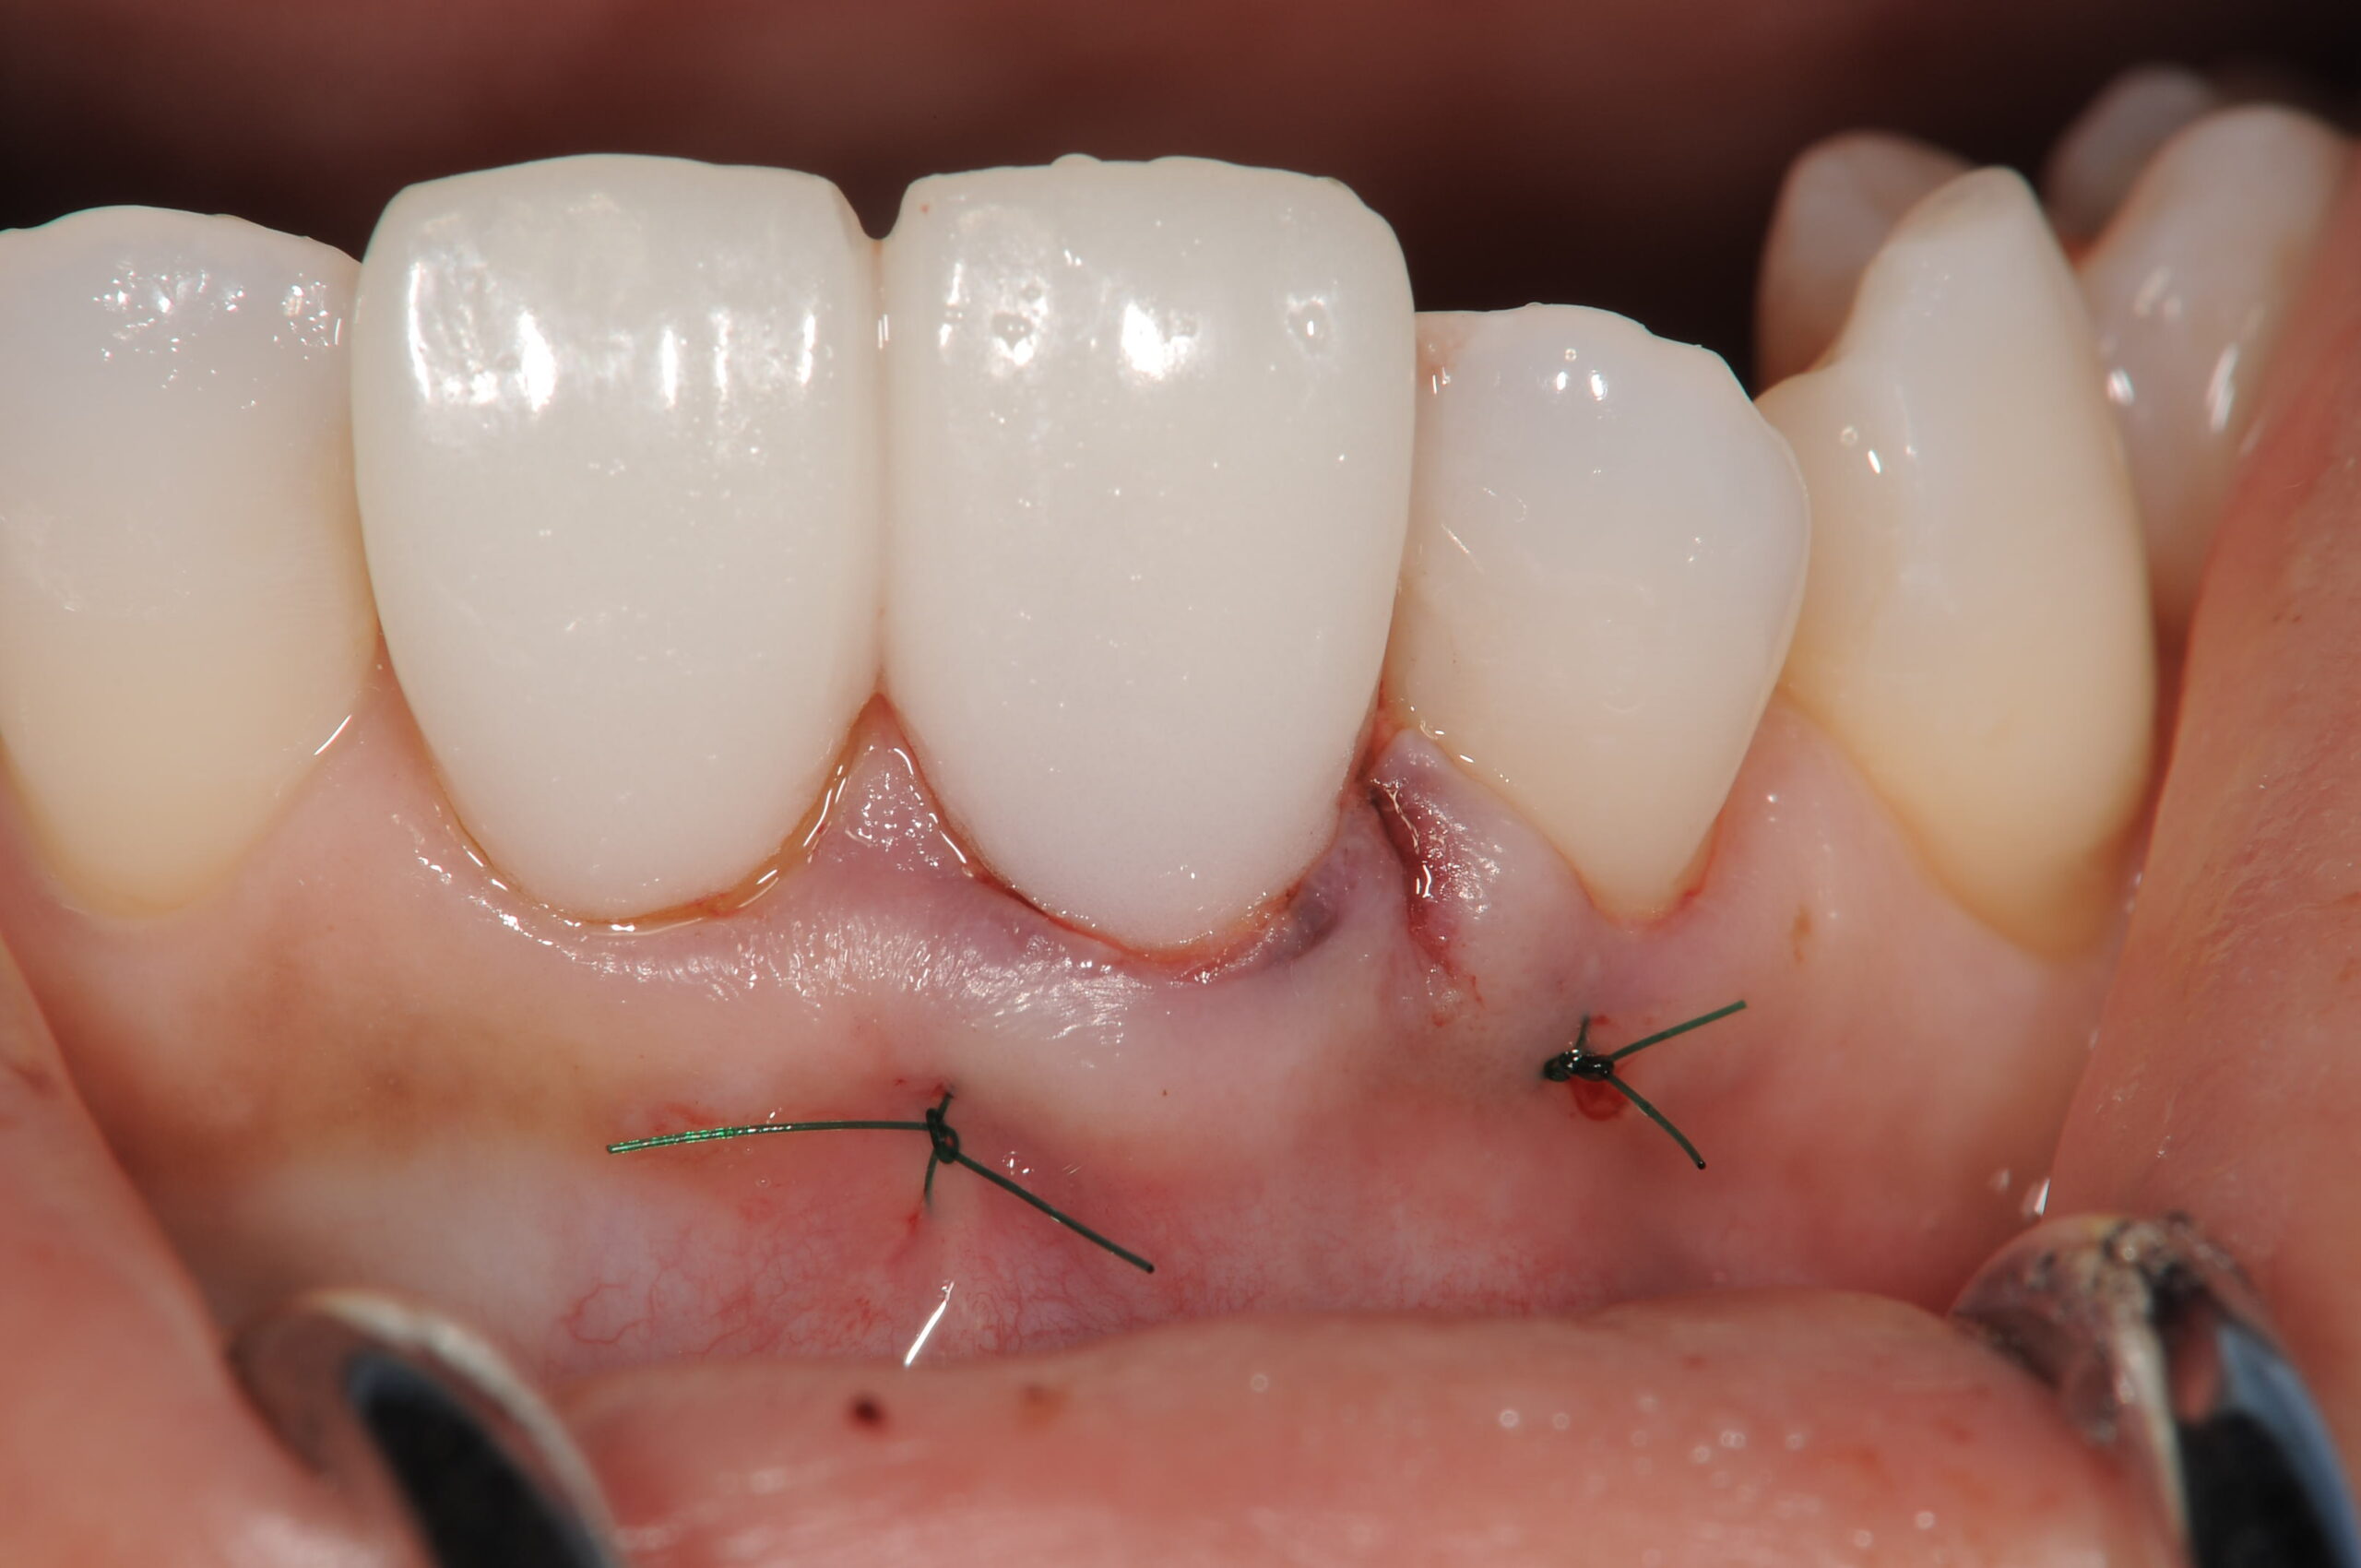

根面上にエムドゲインを塗布する同時に結合組織を移植します。

歯茎を引き上げて、中に結合組織を入れてオペが終了した状態です。